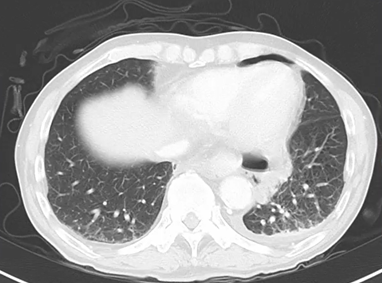

左胸痛が続くため造影CT施行。

縦隔条件

所見:

前頚部に気腫、食道周囲に気腫、わずかに気胸も見られる。左胸水も見られる。

特発性食道破裂が最も疑われる症例。